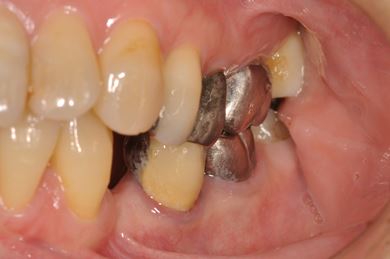

| 性別/年齢 | 女性 / 54歳 | ||||||||||||||||||||||||||||||||

| 主訴 | 下顎の奥歯を抜歯したままになっており、歯茎が少しやせて、両側の歯が少し倒れているような気がする。可能であればインプラントを入れたい。 | ||||||||||||||||||||||||||||||||

| 治療内容 | インプラント1本、メタルボンドセラミック1本 | ||||||||||||||||||||||||||||||||

| 総治療費 | 445,238円 | ||||||||||||||||||||||||||||||||

| 治療期間 | 5ヶ月 |